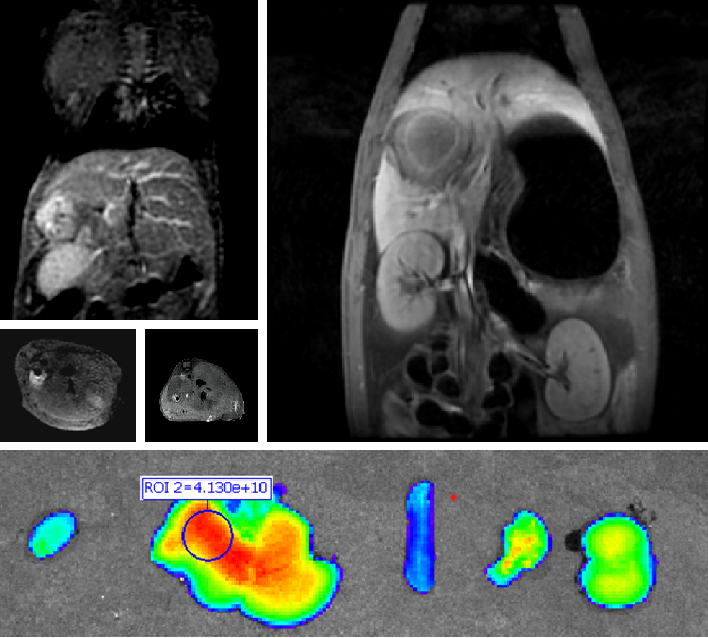

创新纳米药物(PLAT001)

普利制药与浙江大学联合创制的胰腺癌纳米创新药PLAT001,首次构建了γ-谷氨酰转肽酶(GGT)介导的电荷反转聚合物,并将其应用于抗肿瘤药物的递送,突破纳米药物在实体瘤中的渗透性瓶颈。PLAT001目前已经获得中国和美国药物临床试验批件。

PLAT001临床试验获批有望为“癌症之王”胰腺癌的治疗带来重大突破。同时,这也是我国自主研发的首个在美国获批临床试验的纳米药物。今年4月,PLAT001核心专利荣获海南省专利优秀奖。6月24日,浙江大学“高分子递药载体的构筑与功能调控研究”项目获得2023年度国家自然科学奖二等奖,PLAT001项目为该项目重要部分。

创新双模态造影剂(PL002)

普利制药自主研发的双模态造影剂PL002,已经获得美国FDA临床试验批件。PL002的研制首次提出通过整合磁共振技术,弥补现有荧光染料假阳性率高、透射深度有限等的短板,进而提升手术的精确性,降低手术过程中的风险,是全球首个获批临床试验的荧光/磁共振双模态造影剂。本项目预示着海南普利在造影剂领域的长期投入,并致力于开展独具特色的差异化国际化创新发展路径。